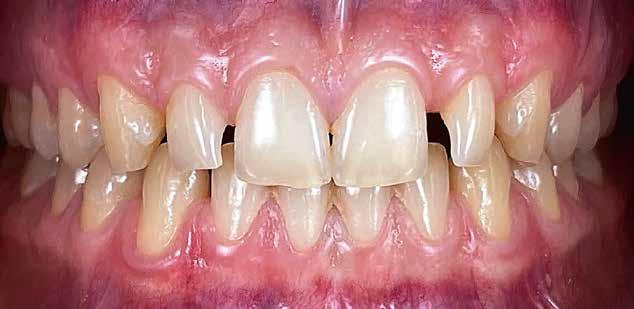

Interdiszciplináris fogászati kezelés myofunkcionális készülék, alignerek és protetikai ellátás alkalmazásával

MED. DENT Abradált frontfogakkal rendelkező felnőtt páciens interdiszciplináris kezelése

A 75 éves páciens új fogsorokat szeretett volna. Felül nem kielégítő teljes lemezes kivehető fogsora volt, alul pedig szintén nem megfelelő részleges fogsora, néhány devitális, apikális oszteolízist és masszív szekunderkárieszt felmutató mutató maradék frontfogon. Az endodonciai beavatkozást a páciens elutasította. Ehelyett kerámiaimplantátumokra alapozott kezelést kívánt. Az úr általános egészségi állapotában panaszok mutatkoztak. A CMD-index nem volt számottevő. A DVT-vizsgálat (1. kép) alapján megállapítható a 42-es fog decens apikális oszteolízise, számottevő vertikális és horizontális csontveszteség a rágóterületen, valamint az

1. kép: Kiindulási helyzet: az OPG hat devitalizált alsó frontfogat ábrázol, részleges apikális oszteolízissel, szekunderkáriesszel, horizontális csontfelszívódással a rágóterületen.